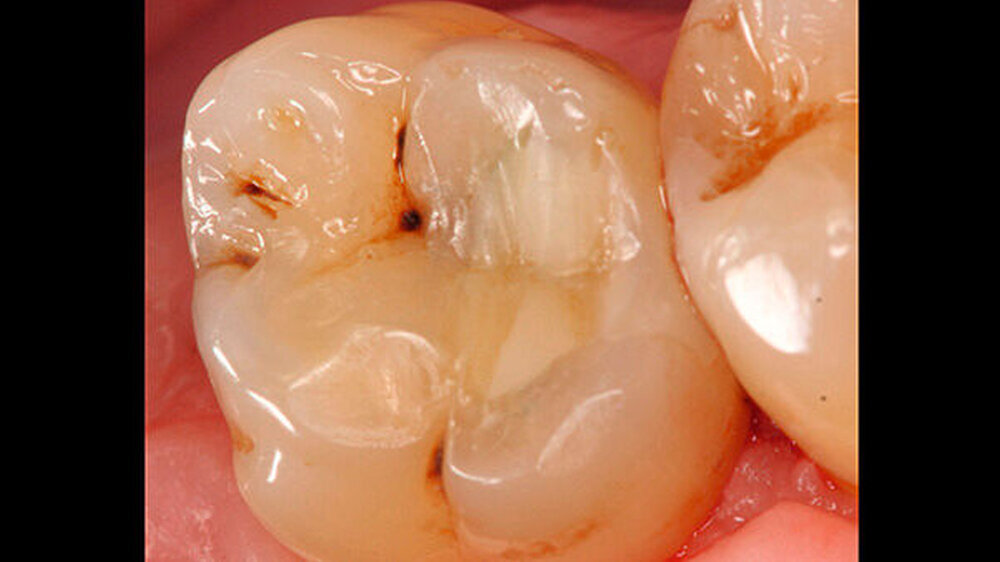

Die Sensibilitätsprüfung des Zahnes 26 auf Kälte mit CO

2

-Schnee war positiv. Die Behandlung wurde auf Wunsch des Patienten ohne Lokalanästhesie durchgeführt. Vor der Präparation erfolgte das Anlegen von Kofferdam an den Zähnen 24 bis 27. Zunächst wurde mit rotierenden Diamantschleifern unter Wasserkühlung von okklusal ein Zugang zum Defekt geschaffen. Der distale Kavitätenbereich wurde mit oszillierenden Instrumenten präpariert (SonicFlex, KaVo) (Abbildung 2). Dabei wurde die Kavität so zierlich wie möglich gestaltet.